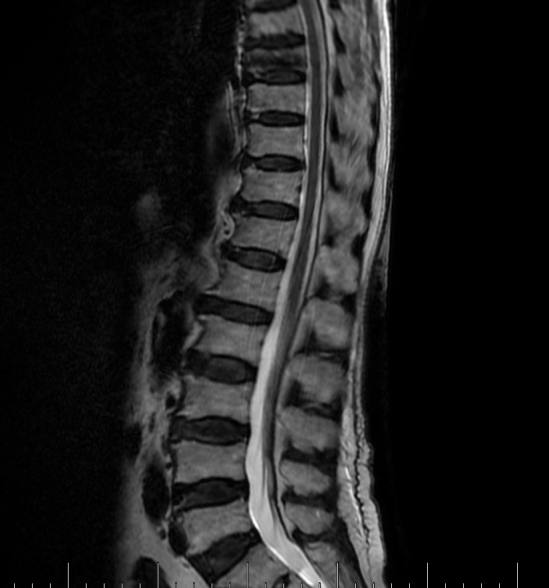

吴老太太今年86岁,同时患有心脏病、老慢支、哮喘、糖尿病等多种疾病,不久前因为并发心衰、呼衰在独墅湖医院经抢救后脱离危险。然而不巧的是,几天前自己在家只轻轻扭了一下腰,就感觉背部疼痛难忍,寝食难安。于是来到我院骨科就诊,医生怀疑是脊柱骨质疏松性骨折,安排收治住院,对病患进行磁共振检查后证实是“第8胸椎压缩性骨折”。

医生在诊断后决定行经皮椎体后突成形术(简称PKP术),需要病人在全身麻醉下俯卧位,医生在全程透视下完成手术。对于一般的患者来说不成问题,而对吴老太太而言却难以实施。首先,她的全身情况较差,心肺功能不全,基础疾病多且严重。入院时就有明显的呼吸困难,氧饱和度只有70%左右,很难耐受全身麻醉。即使勉强度过手术阶段,术后也可能要气管插管,靠呼吸机维持生命,肺部感染则难以控制。其次,如果采用局部麻醉俯卧位手术,尽管可以规避全麻的风险,但该患者根本不能承受俯卧位对心肺功能的影响。但如果不采取手术,卧床以及日夜不停的疼痛对已经遭受过心衰和呼衰的吴老太太来说是雪上加霜。

在常规办法难以实施时,独墅湖医院骨科的医生们决定另辟蹊径,挽救病患生命。常规手术主要面临两大难题:全身麻醉与俯卧位。那么如果采用局部麻醉与侧卧位呢?对!这就是解决问题的关键!局麻可以规避全麻的风险;侧卧可以避免俯卧对心肺的影响。如此,问题似乎迎刃而解了。但是,这样的改变,尤其是侧卧位完成PKP术,导致空间位置变了,手术的难度大大增加了。而且,吴老太太耳背,局麻侧卧位手术需要病人的配合,术中的沟通也是一个问题。尽管困难重重,这也是挽救老人家生命的唯一可行的办法。